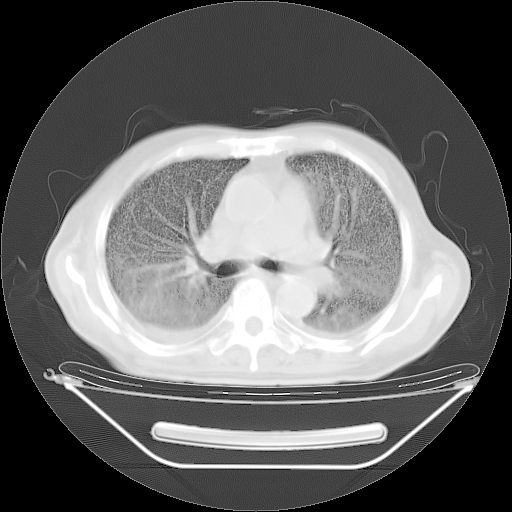

今天复查肺部CT,发现双肺广泛磨玻璃样改变。所以我把3月19日和5月9日相隔50天的肺部CT上传。请大家会诊。

5月9日肺部CT(在4月27日齐鲁医院肺部CT描述部分肺组织磨玻璃样改变,12天后肺组织广泛磨玻璃样改变)

2009年5月9日肺部CT